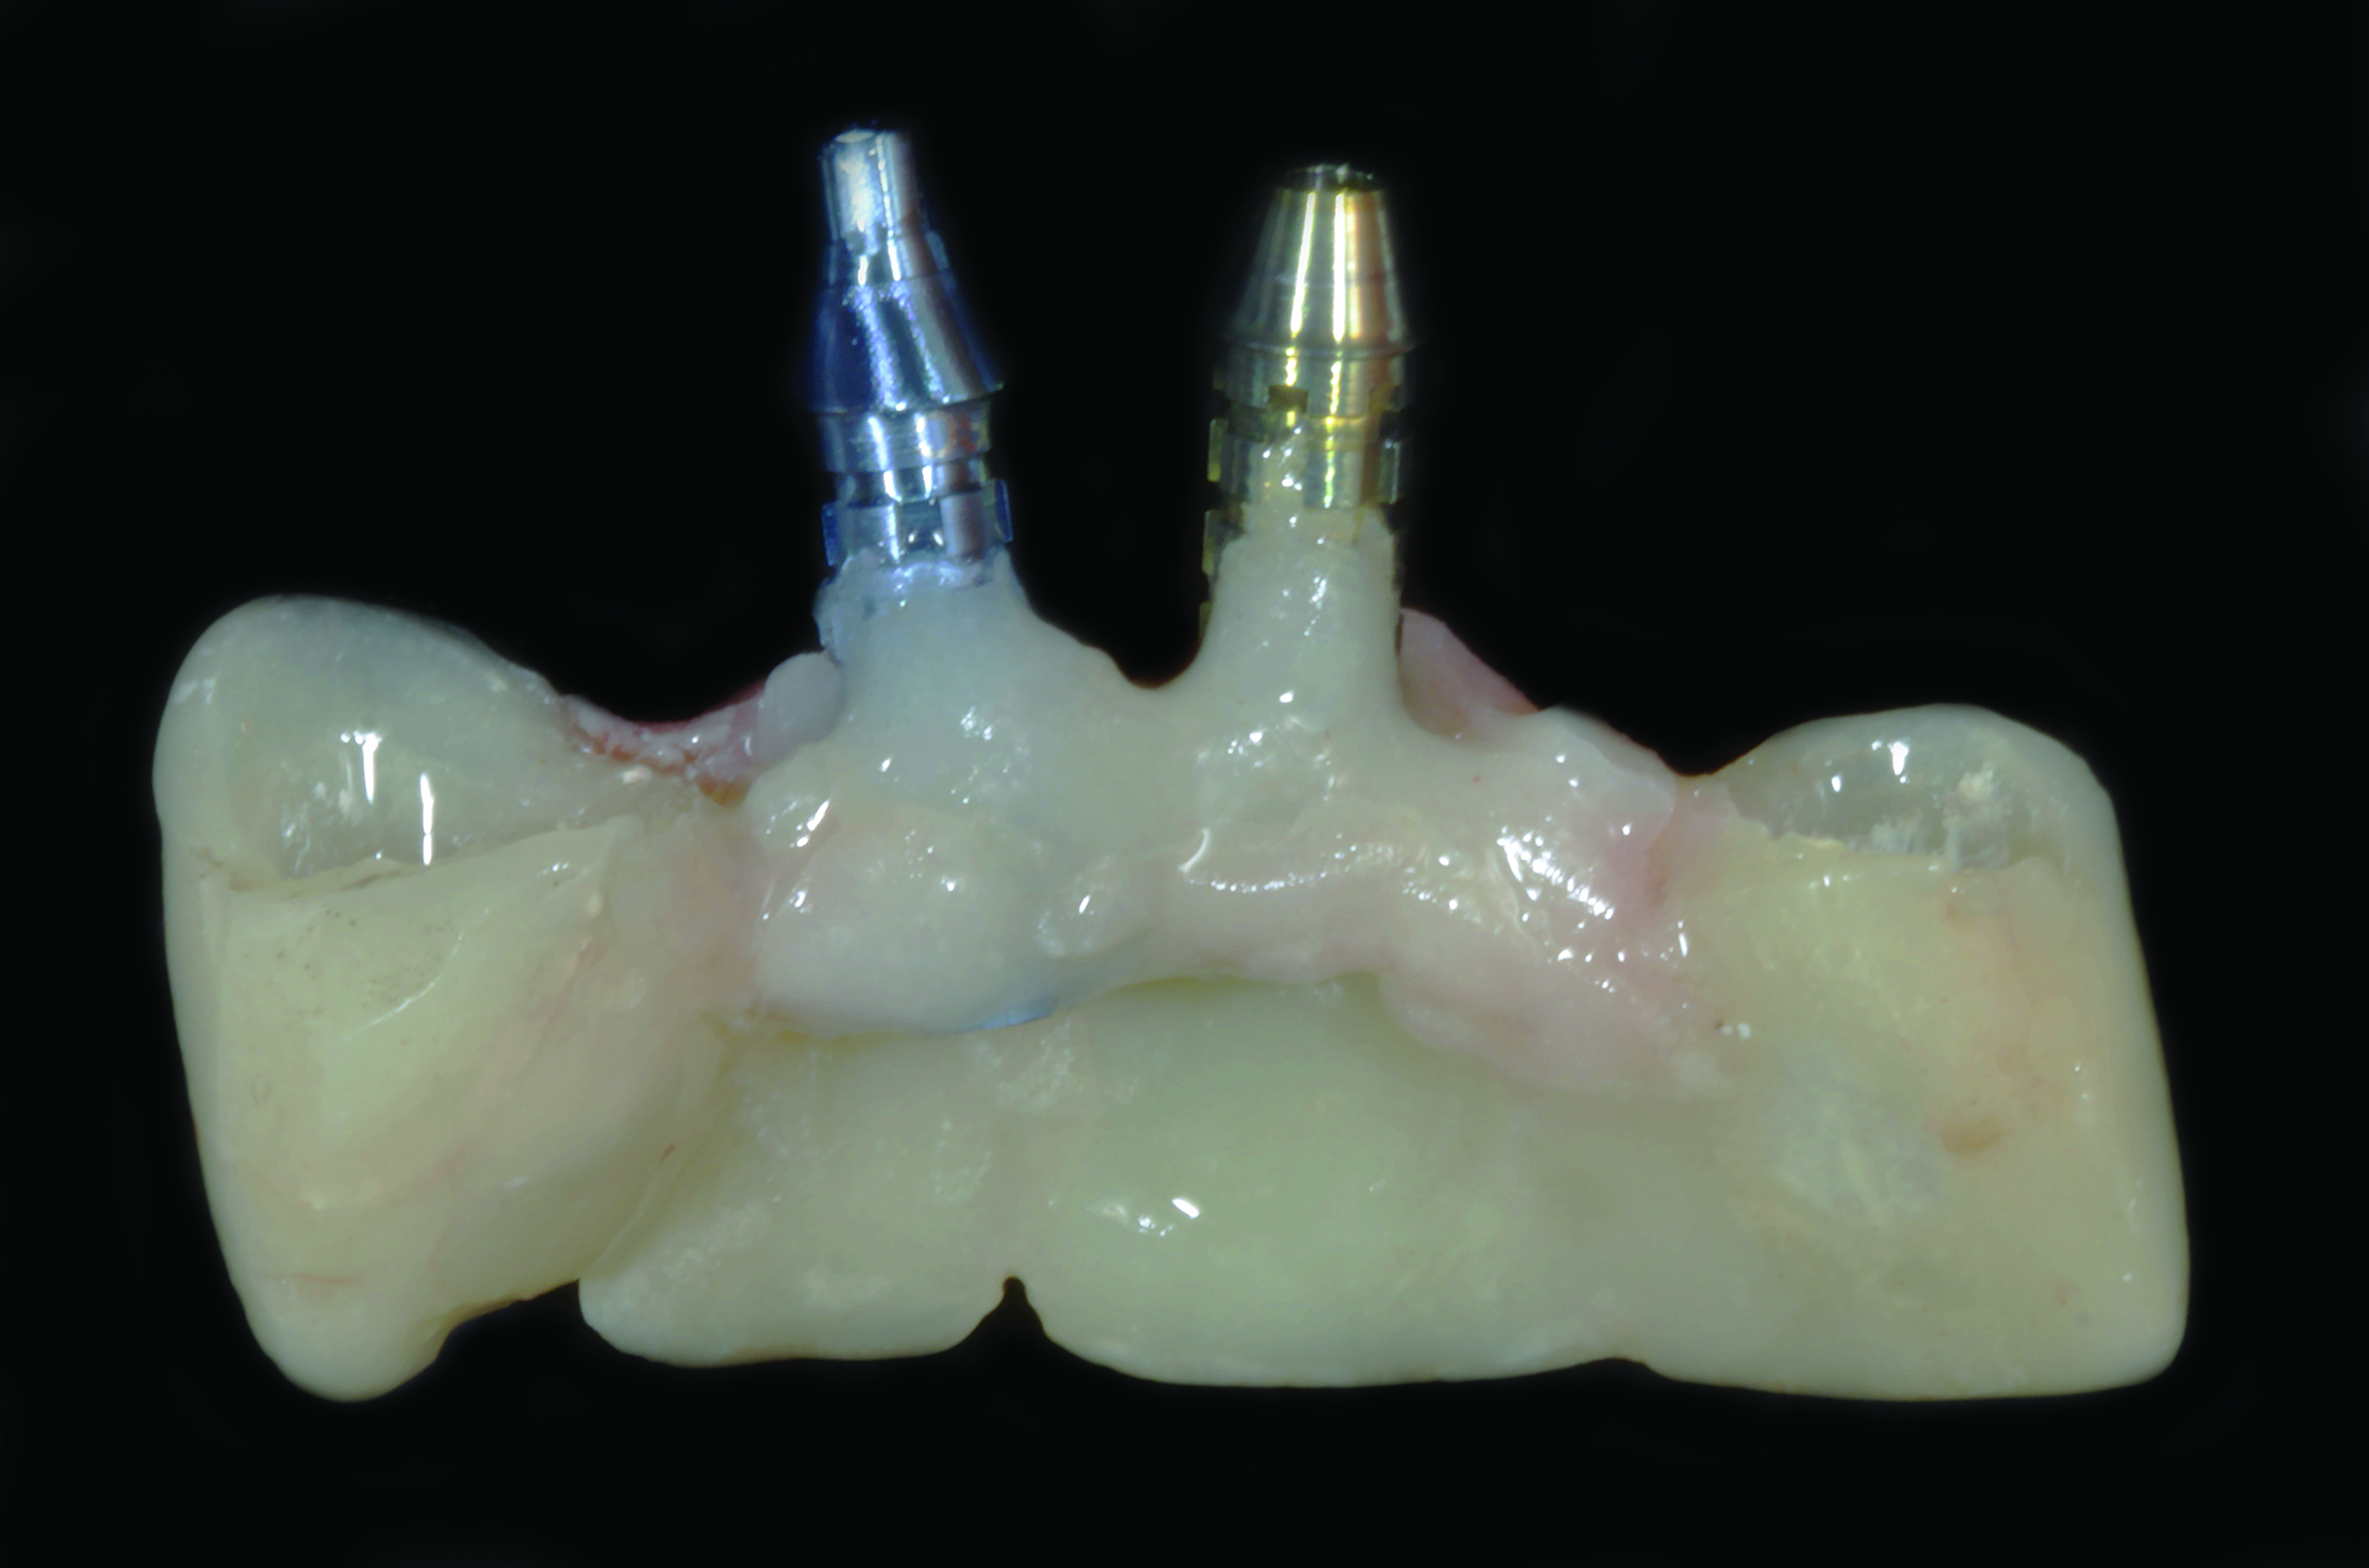

Fig 9. This screw-retained implant-supported provisional prosthesis is laboratory-processed.

Figure 9